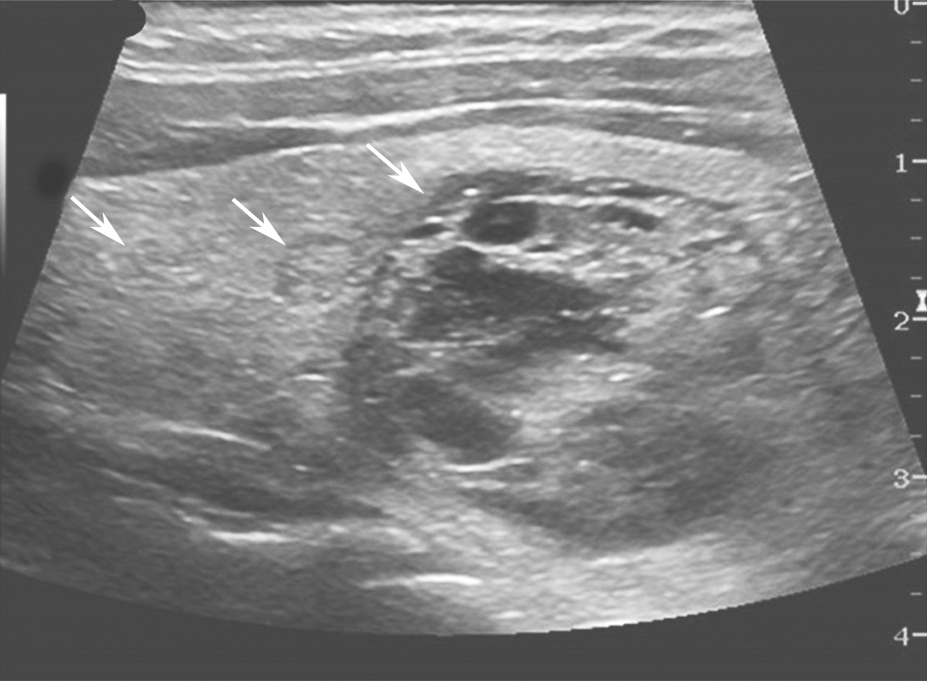

甲状腺腺瘤超声上表现为圆形或椭圆形中等回声或低回声,多伴薄声晕,肿物长轴常与腺体的长轴平行,较大者易合并囊性变、出血或坏死,内可有不规则无回声区、钙化灶或浓缩胶质,浓缩胶质表现为点状强回声后方伴“彗星尾”征,此为良性结节的特征性表现。多数腺瘤内部可见丰富规则的血流信号,周边常见较为完整的环绕血管(图7、图8)。

图7颈部正中偏左横切面:甲状腺左叶中等回声,形态规则、边界清晰,伴薄声晕(箭头所示)。T:气管;L-CCA:左侧颈总动脉

图8颈部正中偏左横切面(与图3-3-7同患者、同切面):中等回声可见丰富规则彩色多普勒血流信号(箭头所示)